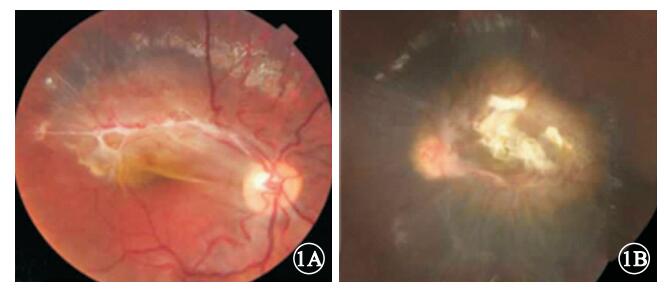

FFA檢查發現,造影早期即可見所有患眼病變部位及其周圍脈絡膜背景熒光均減弱,且其持續存在于整個造影過程中;靜脈期可見因纖維膜收縮、牽引而呈螺旋樣紆曲的視網膜血管走行;病灶處視網膜毛細血管擴張、熒光素滲漏,病變部位熒光亮度逐漸增強(圖 3,4)。均未發現視網膜出血、滲出、毛細血管無灌注區、視網膜新生血管及脈絡膜新生血管等異常。

SD-OCT檢查發現,所有患眼病變部位視網膜內層結構不清、增厚,呈強弱不均勻反射信號,以病灶表面纖維膜處反射信號最強;視網膜色素上皮(RPE)及光感受器內外節連接(IS/OS)等外層視網膜組織反射信號不均勻減弱(圖 5)。8只眼中,病灶內存在與RPE相連的膜樣強反射信號1只眼(圖 5A),占12.5%;因病灶表面纖維膜致密,導致其下方病灶內反射信號被屏蔽形成空洞樣弱信號2只眼(圖 5B),占25.0%。

FFA檢查發現,造影早期即可見所有患眼病變部位及其周圍脈絡膜背景熒光均減弱,且其持續存在于整個造影過程中;靜脈期可見因纖維膜收縮、牽引而呈螺旋樣紆曲的視網膜血管走行;病灶處視網膜毛細血管擴張、熒光素滲漏,病變部位熒光亮度逐漸增強(圖 3,4)。均未發現視網膜出血、滲出、毛細血管無灌注區、視網膜新生血管及脈絡膜新生血管等異常。

SD-OCT檢查發現,所有患眼病變部位視網膜內層結構不清、增厚,呈強弱不均勻反射信號,以病灶表面纖維膜處反射信號最強;視網膜色素上皮(RPE)及光感受器內外節連接(IS/OS)等外層視網膜組織反射信號不均勻減弱(圖 5)。8只眼中,病灶內存在與RPE相連的膜樣強反射信號1只眼(圖 5A),占12.5%;因病灶表面纖維膜致密,導致其下方病灶內反射信號被屏蔽形成空洞樣弱信號2只眼(圖 5B),占25.0%。